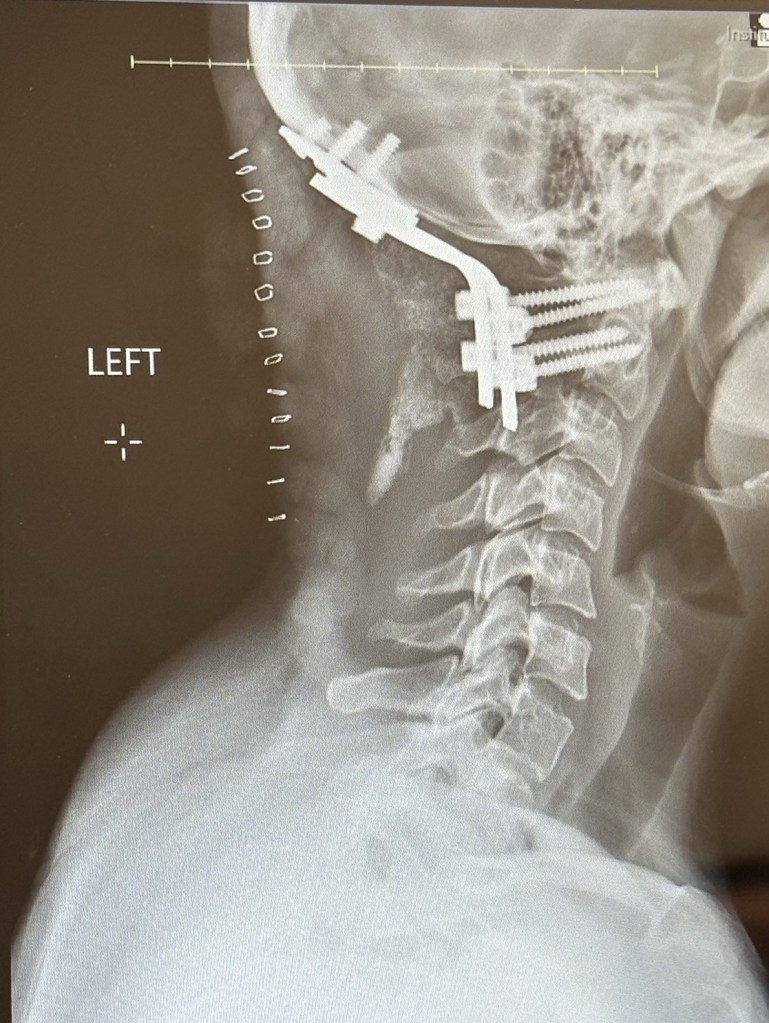

I got new x-rays and my staples out!! There was absolutely no damage when I fell. I just need to move slower. The skin around the staples was tender and ready for them to come out, so it was not that painful. I was able to have my neck brace off for a few mins while they took the staples out and examined the scar. Everything looks good. The scar is hard, but that’s because they retracted the muscles during surgery so they are cramping now and readjusting.

Today they looked over my x-ray and said that everything is okay after the fall. The brace kept everything in place. I also got a special brace for the show, more uncomfortable than the regular one, and I got some replacements covers for the brace so it won’t get gross. The brace goes directly over my incision so we have to keep it really clean.